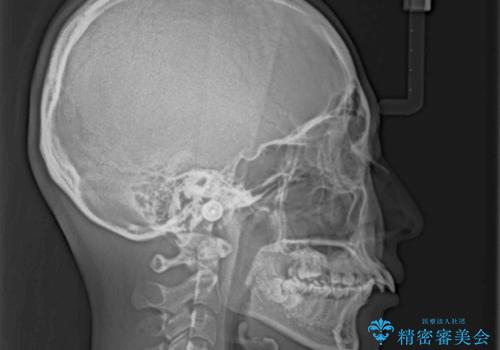

- 飛び出した上顎前歯を気にして来院された患者様です。

下顎は左右2番目の歯が2本欠損しており、上下前歯の前後的な位置は著しくずれている状態でした。

骨格的にも上顎骨が前突傾向にあり、極端な過蓋咬合になっていました。

強い咬合力に抵抗するように歯を動かす必要があるにもかかわらず、上顎第一大臼歯が1本欠損しているため、治療は困難を極めることが予想されました。

上顎前突を改善するために上顎左右第一小臼歯を抜歯し、補助装置を用いて上顎臼歯が前方に移動しないように工夫しながら、表側のワイヤー装置にて歯列を整えていくこととしました。